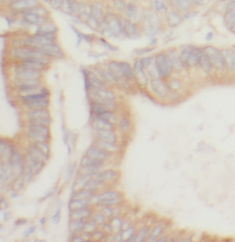

Immunohistochemistry of paraffin-embedded human colon using FNab09563(YES1-Specific antibody) at dilution of 1:50 IP Result of anti-YES1-Specific (IP:FNab09563, 4ug; Detection:FNab09563 1:300) with human placenta tissue lysate 1520ug.